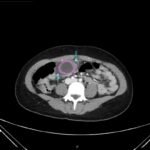

An 18-year-old female presented to the emergency department (ED) with two days of right lower quadrant pain and associated nausea and emesis. After relevant information was gathered and with physical exam findings of a tender right lower quadrant, positive psoas sign, positive Rovsing sign, and pain with right heel tap, the patient was presumed to have appendicitis. However, imaging contradicted the initial leading diagnosis and revealed a markedly distended, hydropic gallbladder with its tip near the umbilicus. Findings of the distended gallbladder with marked wall thickening and pericholecystic fat stranding and edema confirmed acute cholecystitis, and the patient was taken by general surgery for cholecystectomy. Together, this unusual presentation and this unexpected diagnosis shine light upon another facet of the hydropic gallbladder while also serving as a salient reminder to contemplate a broad differential regardless of seemingly classic presentations of illnesses.